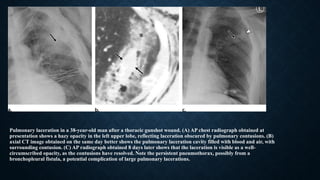

Pulmonary laceration in a 38-year-old man after a thoracic gunshot wound. (A) AP chest radiograph obtained at

presentation shows a hazy opacity in the left upper lobe, reflecting laceration obscured by pulmonary contusions. (B)

axial CT image obtained on the same day better shows the pulmonary laceration cavity filled with blood and air, with

surrounding contusion. (C) AP radiograph obtained 8 days later shows that the laceration is visible as a well-

circumscribed opacity, as the contusions have resolved. Note the persistent pneumothorax, possibly from a

bronchopleural fistula, a potential complication of large pulmonary lacerations.